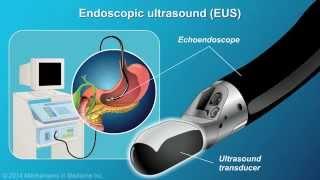

Endoscopy Procedures | Endoscopic Ultrasound (EUS)

EUS evaluation of pancreas and surrounding structures (from Duo bulb)

Midas Gastro